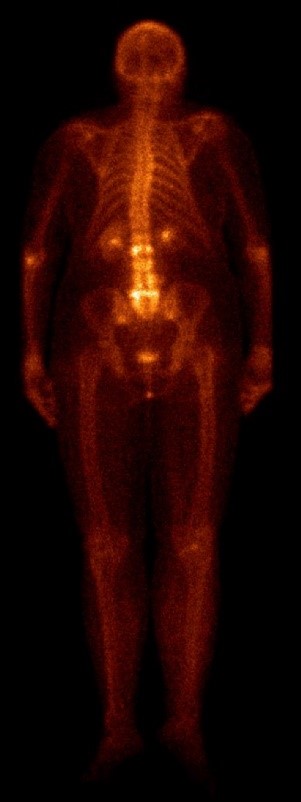

Scyntygrafia kośćca

Scyntygrafia kośćca umożliwia wczesne wykrycie i monitorowanie przebiegu chorób związanych z kośćmi. Dużą zaletą tego badania jest jego wysoka czułość oraz możliwość zobrazowania całego ciała podczas jednej sesji. Najczęściej stosuje się do oceny procesów wywołanych przez nowotwory, takich jak przerzuty do kości. Istnieje również wiele nieonkologicznych wskazań jak ocena obluzowania protez stawowych, ocena aktywności metabolicznej zmian zobrazowanych w tomografii komputerowej bądź rezonansie o nieznanych charakterze, ocena złamań przeciążeniowych, zmian zwyrodnieniowych oraz dla wyjaśnienia przyczyny bólów kostnych.

| Anterior | Posterior |